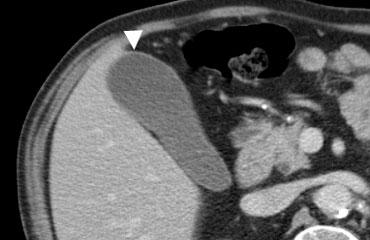

Bên trái là hình ảnh của bệnh nhân nam 71 tuổi với viêm túi mật u hạt vàng.

CT có thuốc cản quang cho thấy thành túi mật biến dạng và dày, chứa các nốt giảm tỷ trọng.

Các nốt này đại diện cho các ổ áp xe hoặc ổ viêm.